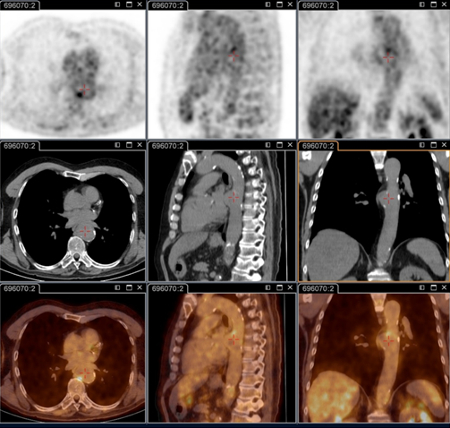

18F-fluorodeoxyglucose (FDG) PET/CT imaging

Test

Critical for identifying persistent focalised infections.[80]

Is able to decipher endocarditis, vascular infection, lymphadenitis, and osteoarticular infection; these conditions cannot be identified without this technique.

It is now part of the standard anatomical check-up in patients with persistent symptoms, and/or persistent elevated serology, and/or positive polymerase chain reaction on blood/serum, or any sample with clinical presentation not consistent with primary infection.[3]

It is specifically recommended for patients: with acute Q fever with persisting phase 1 IgG ≥1:800 and/or sign of bad evolution; with acute Q fever with a history of vascular graft or aneurysm; or with unexplained (phase 1 IgG ≥1:800) serology or clinical suspicion of a persistent infection.

Also useful for identifying infection in patients with vascular prosthesis and/or aneurysm, and identifying those who require surgery with resection of infected vascular tissues. [Figure caption and citation for the preceding image starts]: Q fever endocarditis diagnosed at PET scan: 18F-fluorodeoxyglucose PET/CT. In this asymptomatic patient with heart valve history with elevated serology, the PET scan diagnosed an aortic endocarditis on native valve with thoracic and lumbar aortic mycotic aneurysmsInstitut Hospitalo-Universitaire Méditerranée Infection (patient consent obtained) [Citation ends].

[Figure caption and citation for the preceding image starts]: Q fever aortic mycotic lumbar aneurysm diagnosed at PET scan: 18F-fluorodeoxyglucose PET/CT. In this asymptomatic patient with heart valve history with elevated serology, the PET scan diagnosed an aortic endocarditis on native valve with thoracic and lumbar aortic mycotic aneurysmsInstitut Hospitalo-Universitaire Méditerranée Infection (patient consent obtained) [Citation ends].